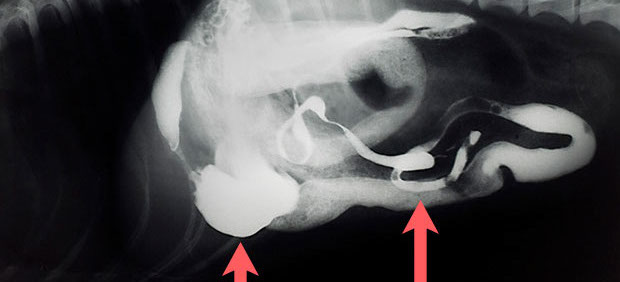

Harnsteine mit Harnblase und Harnröhre (Katheter stößt auf die Steine)